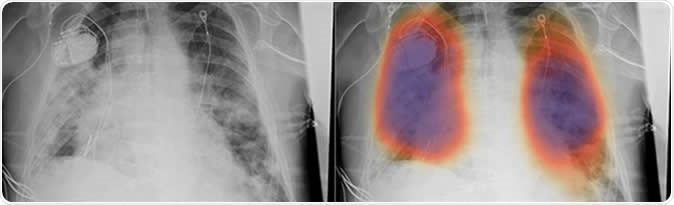

Chest X-rays from a patient with COVID-19 pneumonia, original x-ray (left) and AI-for-pneumonia result (right). Patient has a pacemaker device and an enlarged heart, which indicates that the AI algorithm is powerful enough to work even when the patient has underlying health issues.

The new algorithm overlays X-rays with color-coded maps to detect pneumonia. It has been trained with about 22,000 notations by human radiologists. To test their algorithm, the team used the artificial intelligence approach to ten chest X-rays from five patients in China and the United States with COVID-19. The ten images were published in medical journals.